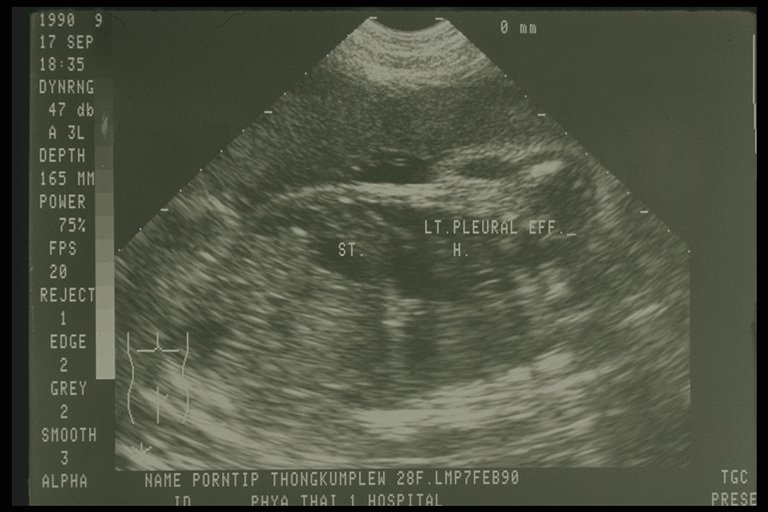

Prenatal ultrasonography showed bilateral congenital chylothorax, massive pleural effusion was detected in both chest cavity